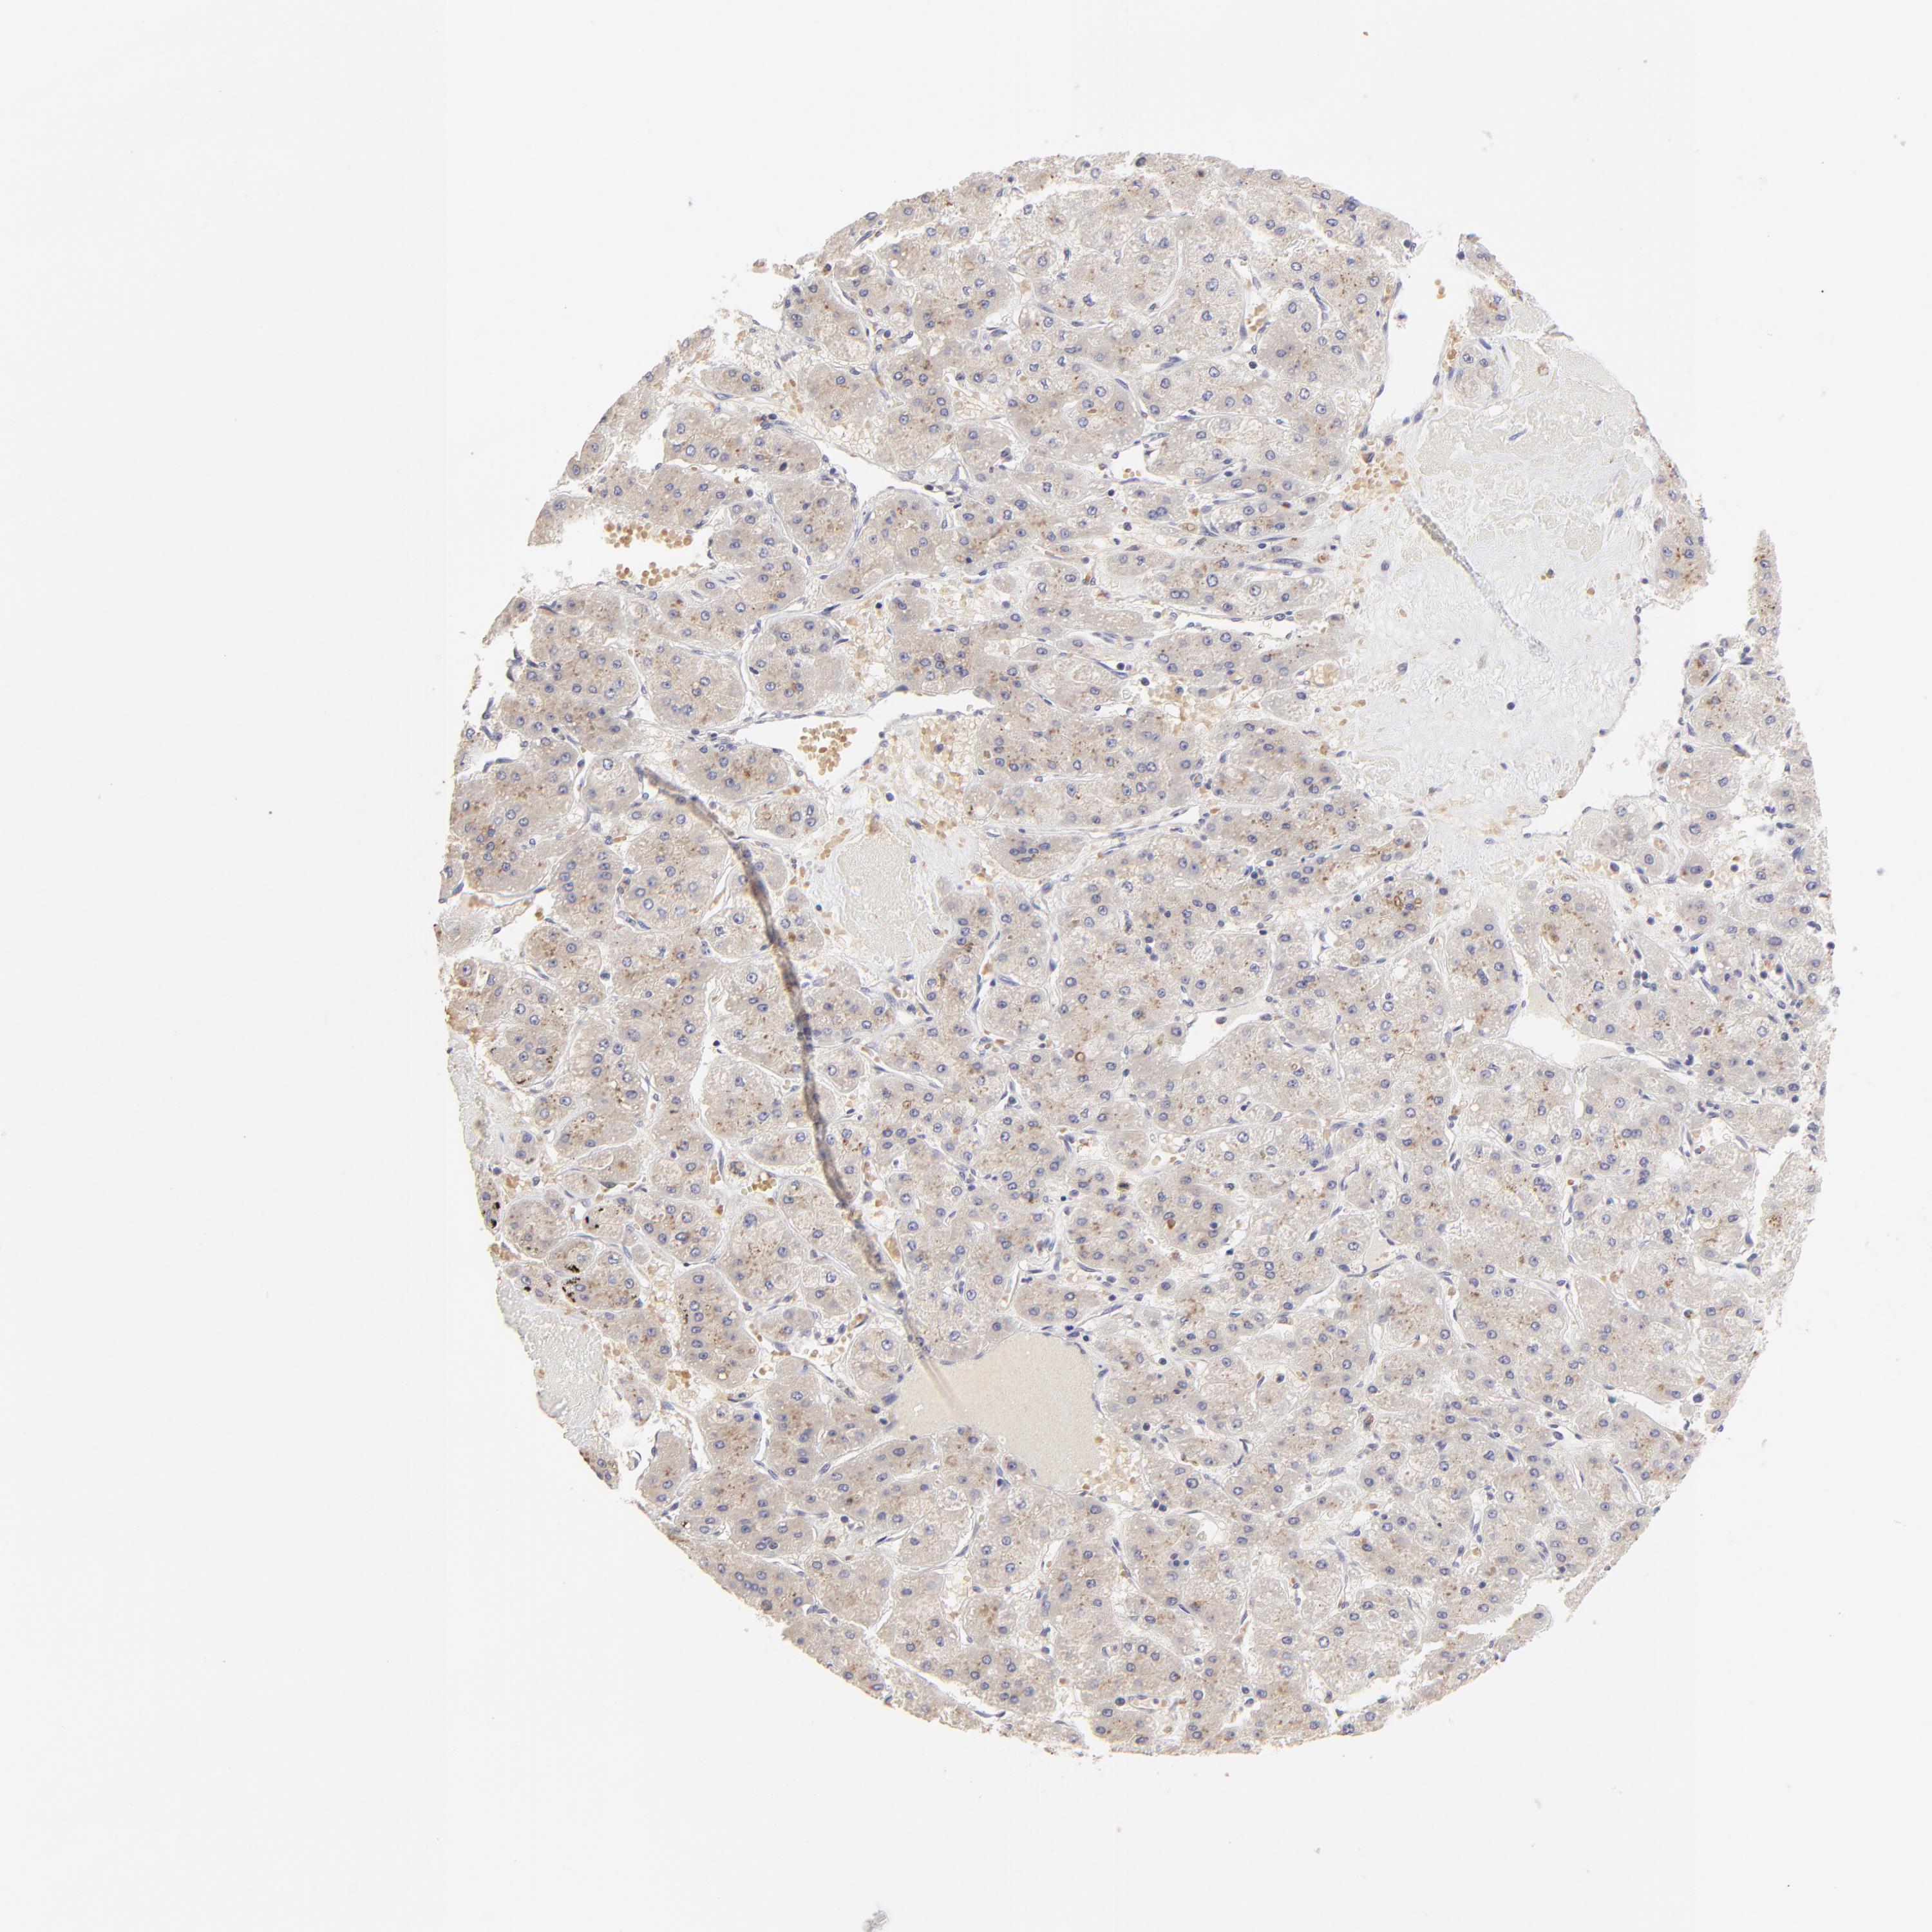

LIVER CANCER - Protein expressioni

A mouse-over function shows sample information and annotation data. Click on an image to view it in a full screen mode. Samples can be filtered based on level of antibody staining by selecting one or several of the following categories: high, medium, low and not detected. The assay and annotation is described here.

Note that samples used for immunohistochemistry by the Human Protein Atlas do not correspond to samples in the TCGA dataset.

Antibody stainingi

Antibody staining in the annotated cell types in the current human tissue is reported as not detected, low, medium, or high, based on conventional immunohistochemistry profiling in selected tissues. This score is based on the combination of the staining intensity and fraction of stained cells.

Each image is clickable and will lead to virtual microscopy that enables deeper exploration of all samples and also displays staining intensity scores, fraction scores and subcellular localization as well as patient and tissue information for each sample.

Antibody HPA003141

Staining

High

Medium

Low

Not detected

Intensity

Strong

Moderate

Weak

Negative

Quantity

>75%

75%-25%

<25%

None

Location

Nuclear

Cytoplasmic/membranous

Cytoplasmic/membranous,nuclear

Carcinoma, Hepatocellular, NOS

Cholangiocarcinoma